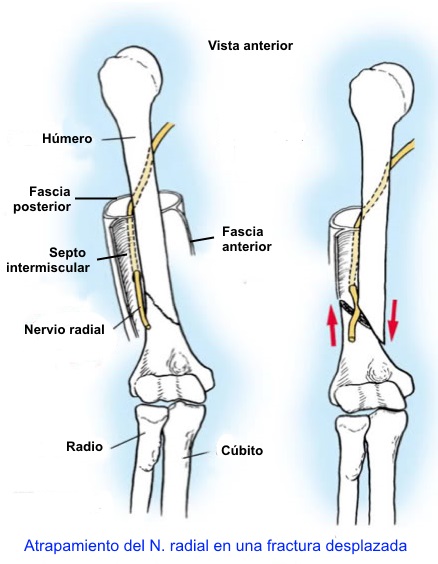

- Septo intermuscular lateral del brazo, especialmente cuando se producen fracturas desplazadas de húmero.

La parálisis del nervio radial en el

brazo con mayor frecuencia es causada por la fractura del húmero,

especialmente en el tercio medio (fractura de Holstein-Lewis) o en

la unión de los tercios medio y distal. El nervio puede ser

comprimido por el tabique intermuscular lateral. Esta parálisis

puede aparecer de forma aguda en el momento de la lesión, secundaria

a la manipulación de la fracturar, o de un callo exuberante. Otras

causas menos comunes de la parálisis del nervio radial en el brazo

incluyen la compresión en el arco fibroso de la cabeza lateral del

músculo tríceps y compresión por un músculo accesorio

subescapular-redondo mayor-dorsal.